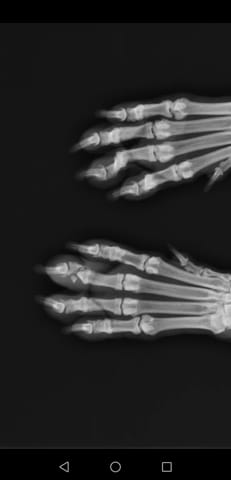

Je reviens d'une promenade rivière avec boo ma bull terrier après 15jours de collerette à cause d'un othematome à l'oreille gauche (qui succède à deux opérations à cause d'un othematome récidivant à l'oreille droite) non contente de sortir elle a sauter dans l'eau et à bien profitée mais en rentrant la voilà prostrée dans son panier et je vois qu'entre ses "orteils" elle est bleue et qu'elle boîte je m'inquiéte car c'est dimanche soir est ce que je dois l'emmener chez le veto de garde ou ça peut attendre demain pensez vous que c'est une fracture pourtant ça n'a pas l'air tordu et elle se laisse manipuler...

Qu'en pensez vous ? J'ai ajouté les photos pour que vous voyez un peu